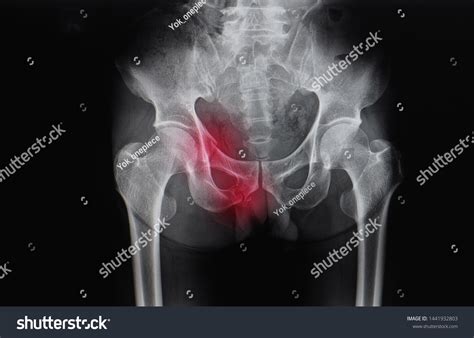

X-Ray The primary imaging tool to visualize bony breaks and alignment.

CT Scan Used for detailed cross-sectional views if the X-ray is unclear or if complex fractures are suspected.

• Pelvis X-ray Fracture